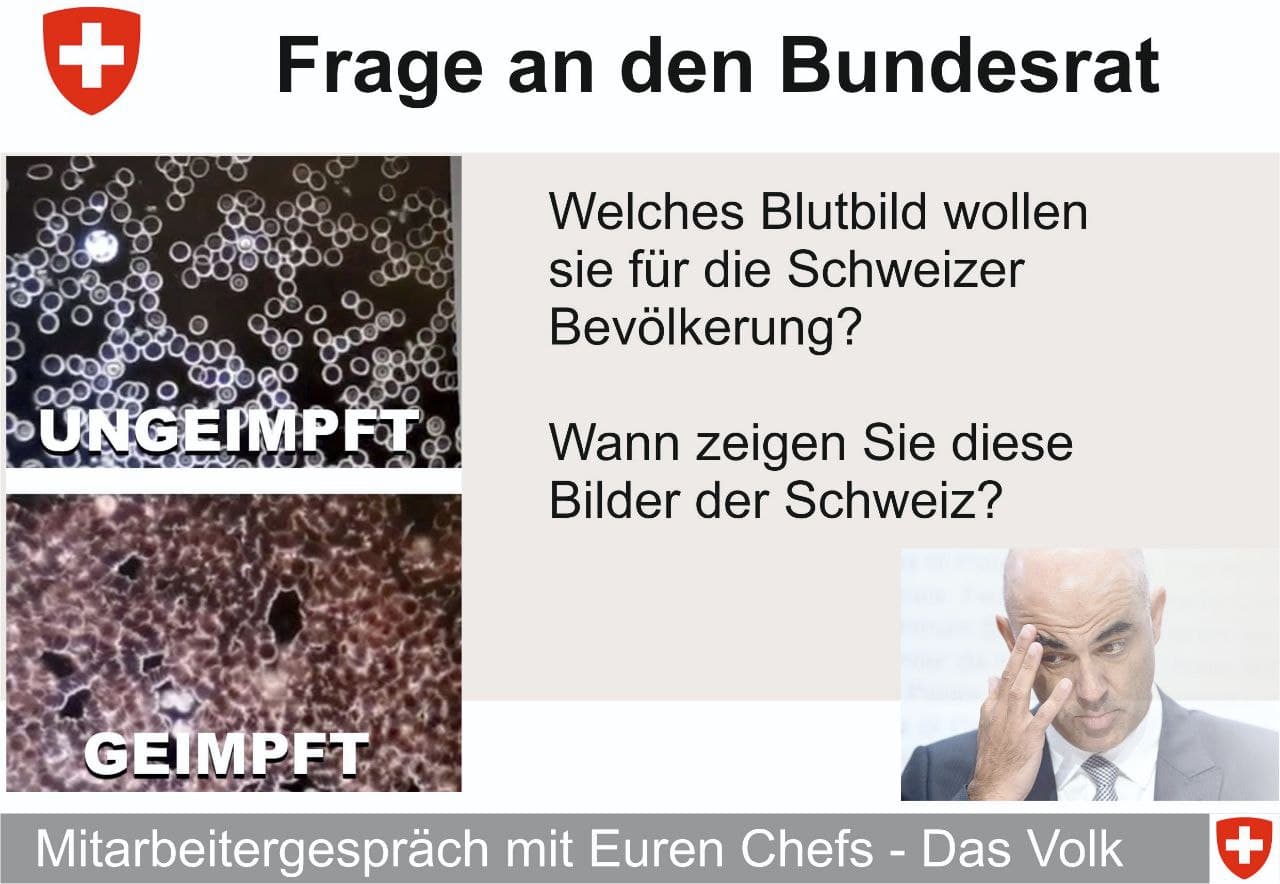

GENimpfschaden Blutbild

3.12.2021: Gesundes Blut verglichen mit zerstörtem,

GENgeimpftem Blut: Der Lügen-Bundesrat Berset will das

dem Volk verheimlichen!

Impfschäden Schweiz Coronaimpfung, [03/12/2021 11:15 P.M.]

https://t.me/Impfschaden_Corona_Schweiz/32874

[Weitergeleitet aus Frag den Bundesrat]

GENimpfschaden Blutbild 3.12.2021: Gesundes Blut

verglichen mit zerstörtem, GENgeimpftem Blut: Der

Lügen-Bundesrat Berset will das dem Volk verheimlichen!